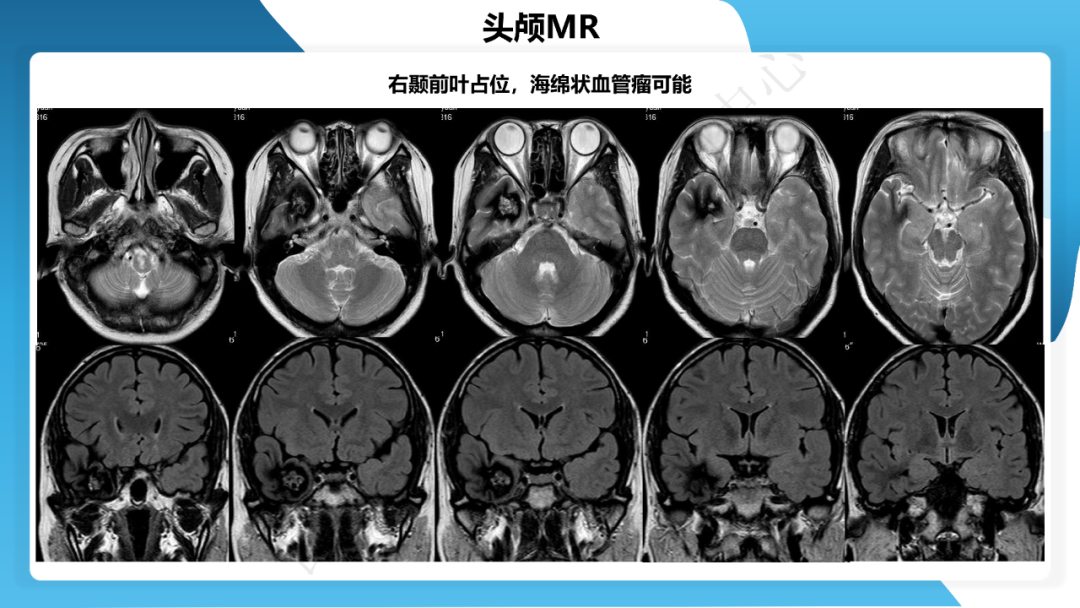

《「痫停」信步》癫痫治疗病例荟萃第三十七期---颞叶海绵状血管瘤相关癫痫的手术治疗一例